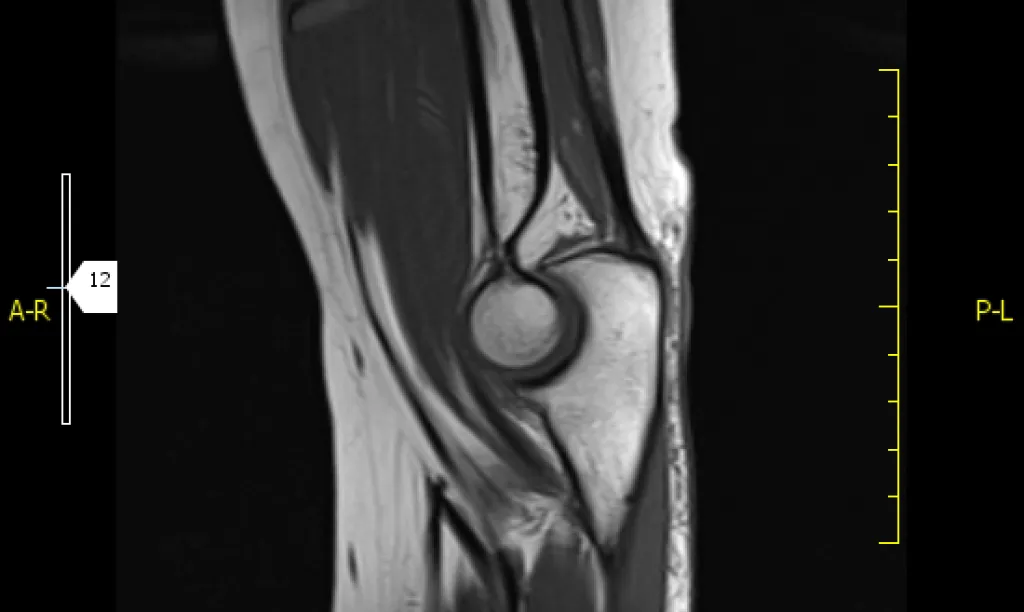

Resonancia magnética 2 regiones anatómicas

La combinación de 2 regiones hace posible el estudio conjunto de caderas y articulación sacroilíaca o valoración de columna dorsal y lumbar.

La resonancia magnética es una prueba irremplazable en la valoración de ciertas áreas anatómicas como el musculoesquelético (rodillas, hombro, caderas…) y neurológicos (columna, cerebral,…).

Se utiliza para todas las áreas del cuerpo y es esencial en musculoesquelético y sistema nervioso.